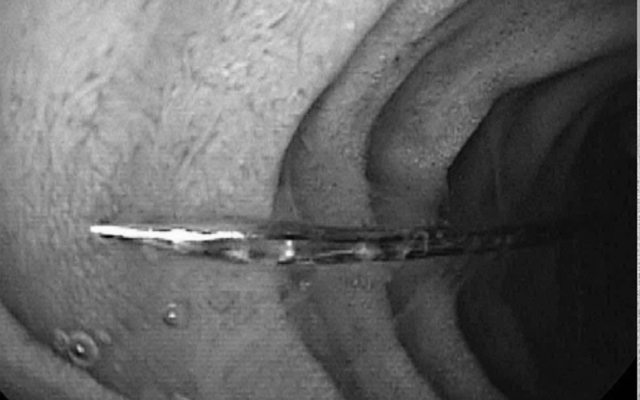

Kim may trong đường tiêu hóa của trẻ. Ảnh BVCC.

Tại bệnh viện, bệnh nhi tỉnh táo, sinh hiệu ổn định. Hình ảnh X-quang cho thấy một dị vật cản quang dạng kim may dài khoảng 4 cm nằm ở đoạn trên ổ bụng. Được biết, bé có tiền sử chậm phát triển tâm thần được chẩn đoán từ 2 năm trước.

Khi đưa ống soi mềm qua đường miệng vào ống tiêu hóa trên, ghi nhận dị vật kim may nằm ở vị trí D2 tá tràng, kèm xước nhẹ niêm mạc hành tá tràng. Dị vật sau đó đã được các bác sĩ gắp ra an toàn. Hiện sức khỏe bé đã ổn định và đang hồi phục tốt.